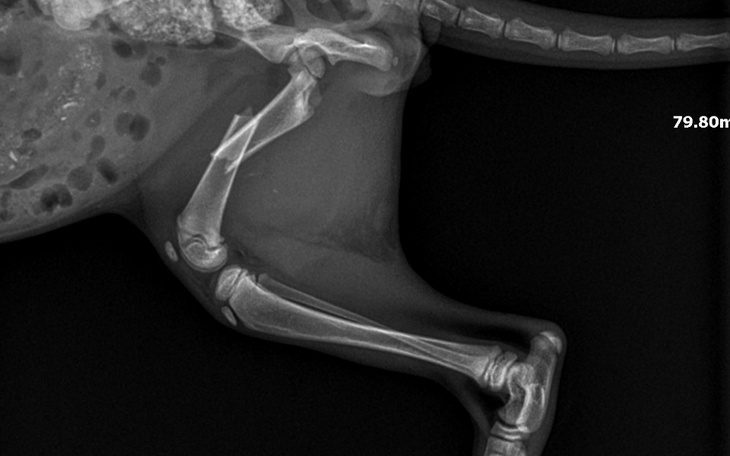

Okazało się, że maluszek cierpi na świerzbowca usznego, koci katar oraz zdiagnozowano również złamaną kość udową. Koszt operacji złamanej kości to 2,500 zł. Niestety nie stać mnie na pełne pokrycie wszystkich kosztów zabiegu.

Zabieg zostanie przeprowadzony przez specjalistę ortopedii w Wieliczce 5 czerwca 2024 roku. Niestety nie można zwlekać zbyt długo z zabiegiem, ponieważ może to doprowadzić kotka do stałego inwalidztwa.

Zabieg ma na celu „złożenie/naprawy” pękniętej kości udowej i doprowadzenie maleństwa do pełnego zdrowia i komfortu podczas ruchu.